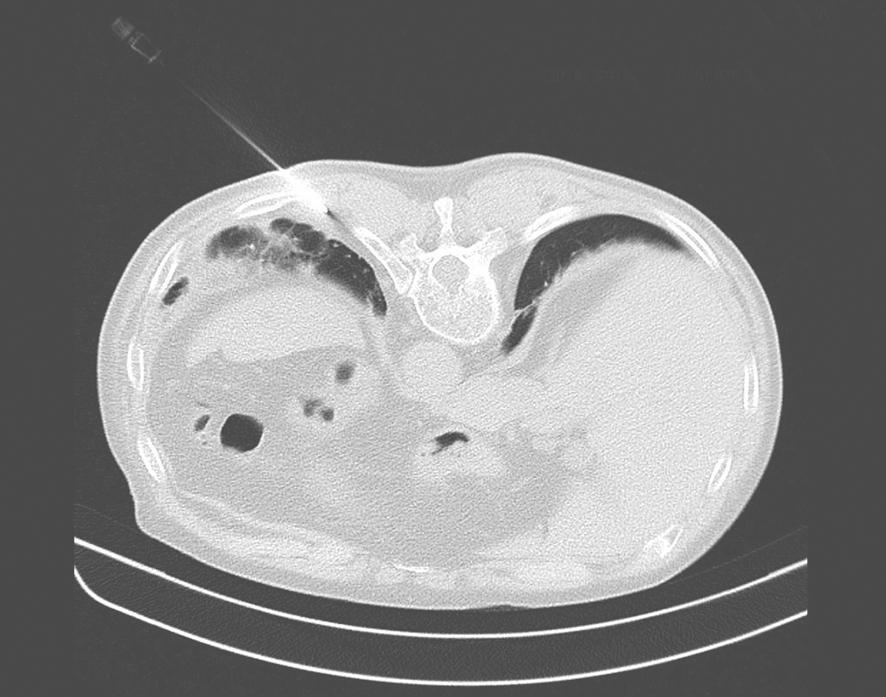

经皮闭式胸膜活检对胸腔积液病因诊断有重要意义,胸膜针刺活检具有简单、易行、损伤性较小的优点,诊断阳性率为40%~75%。CT或超声引导下活检可提高成功率,研究显示CT或超声引导下的胸膜活检(图2-13-4)对恶性胸膜疾病诊断的敏感性达70%~91%。

图2-13-4 CT引导下胸膜穿刺活检